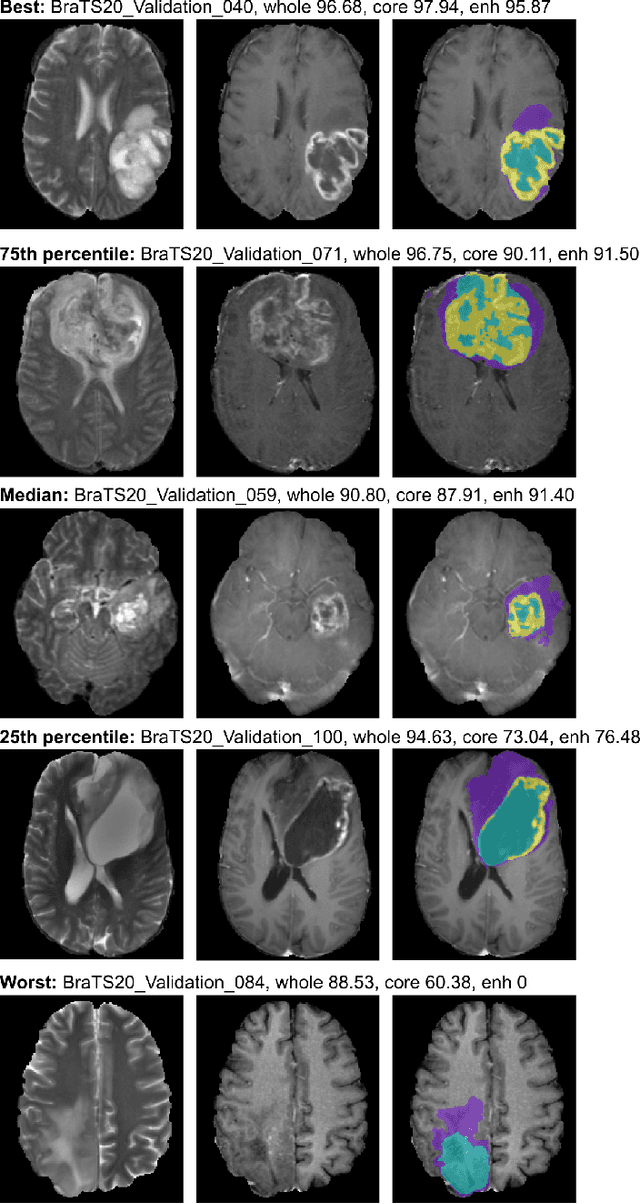

Abstract:We apply nnU-Net to the segmentation task of the BraTS 2020 challenge. The unmodified nnU-Net baseline configuration already achieves a respectable result. By incorporating BraTS-specific modifications regarding postprocessing, region-based training, a more aggressive data augmentation as well as several minor modifications to the nnUNet pipeline we are able to improve its segmentation performance substantially. We furthermore re-implement the BraTS ranking scheme to determine which of our nnU-Net variants best fits the requirements imposed by it. Our final ensemble took the first place in the BraTS 2020 competition with Dice scores of 88.95, 85.06 and 82.03 and HD95 values of 8.498,17.337 and 17.805 for whole tumor, tumor core and enhancing tumor, respectively.